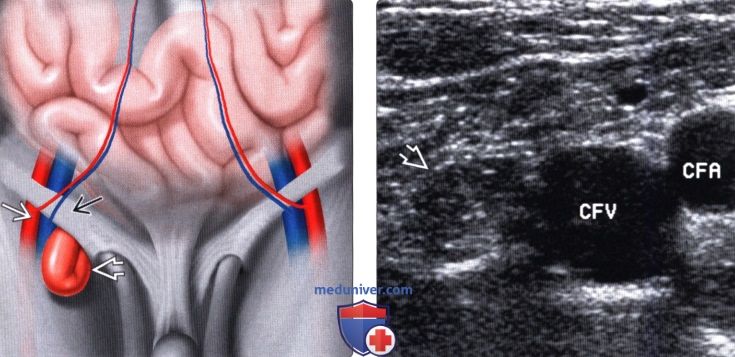

Косая паховая грыжа выходит через наружную паховую ямку, в составе элементов семенного канатика, покрытых наружной семенной фасцией, проходит паховый канал, выходит через наружное отверстие пахового канала и может опускаться в мошонку, растягивая её.

Паховые грыжи могут возникать в любом из двух проходов через нижнюю брюшную стенку, по одному с каждой стороны паха. Эти ходы называются паховыми каналами. Паховые грыжи также могут возникать через два более глубоких паховых прохода, называемых бедренными каналами.Грыжи через эти проходы также известны как бедренные грыжи.

Паховые грыжи чаще всего содержат жир или часть тонкой кишки. У девочек или женщин паховые грыжи могут включать часть женской репродуктивной системы, например яичник. Когда возникает паховая грыжа, часть брюшины — слизистая оболочка брюшной полости — выпячивается через брюшную стенку и образует мешок вокруг грыжи.

Почему паховые грыжи чаще встречаются у мужчин, чем у женщин?Когда самцы развиваются внутриутробно, их яички развиваются вверх в брюшной полости, а затем опускаются в мошонку через паховый канал.Этот канал, изначально очень узкий, позволяет кровеносным сосудам и нервам проходить к яичку. С возрастом паховый канал теряет свою структурную целостность, превращаясь из длинного узкого цилиндра в более короткий и широкий конус. Когда это изменение происходит в мужском паховом канале, увеличенное внутреннее отверстие (внутреннее кольцо) и отсутствие угла конуса позволяют содержимому брюшной полости выступать в паховый канал. Это называется непрямой паховой грыжей. Прямая паховая грыжа возникает, когда прочный слой брюшной стенки (поперечная фасция) растягивается и позволяет содержимому брюшной полости проталкиваться в паховый канал.У женщин паховая анатомия не такая, как у мужчин, и поэтому вероятность развития паховых грыж значительно ниже. Фактически, мужчины составляют 90% пациентов, которым требуется операция на паховой грыже.